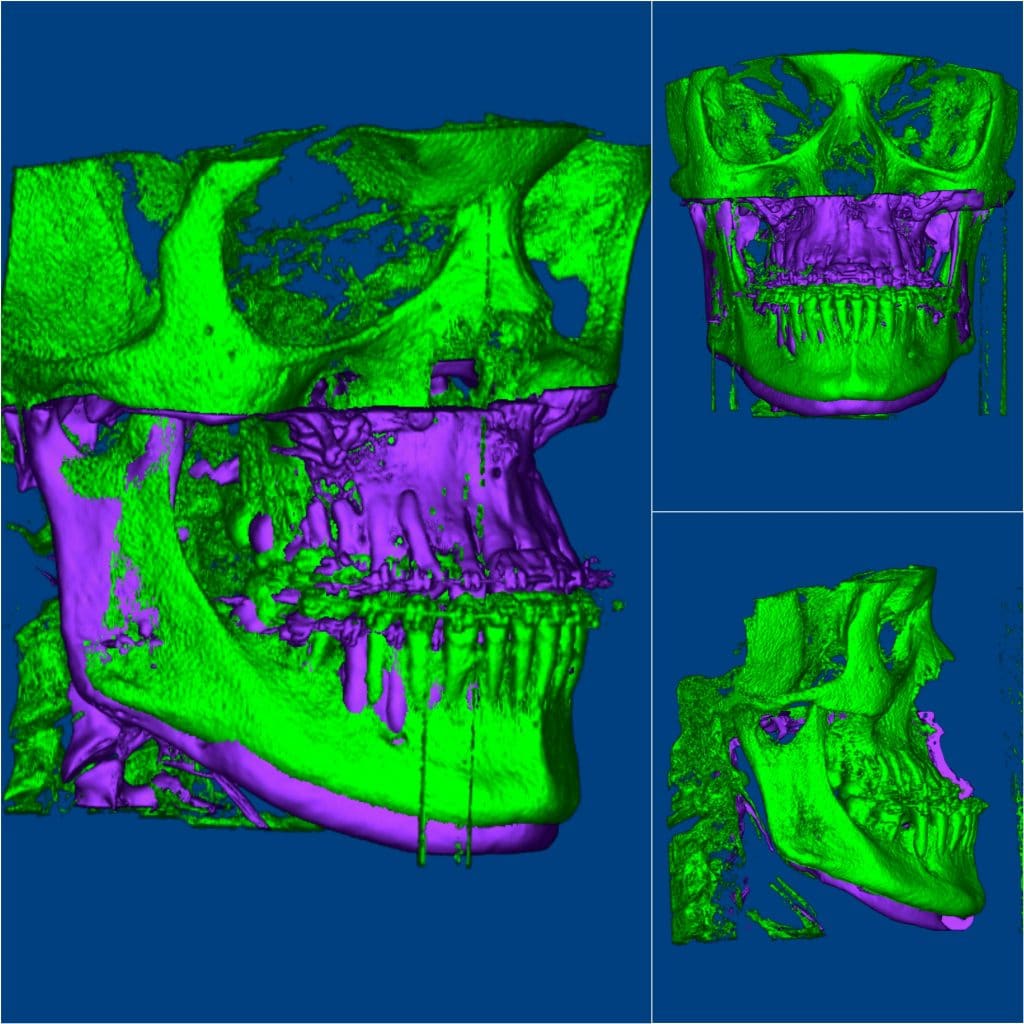

* Extraoral : she has the features of “pfeiffer dyndrome”( one of craniocynestosis syndromes ), concave , class III facial pattern , sever midface deficiency , hypertelorism , broad and malformed thumbs .

*Ttt plan: combined orthodontic and orthognathic surgery

B. Surgery : bimax surgery , modified Lefort 1 osteotomy with maxillary advancement , Bsso with mandibular setback .